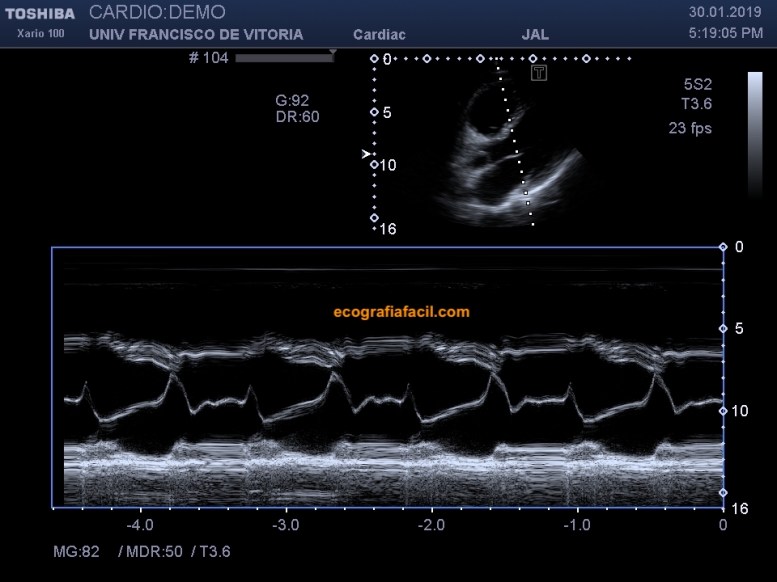

Además de la evaluación en 2D, es común obtener una imagen en modo M que pase por el borde libre de los velos de la válvula mitral y otra que pase por el centro del ventrículo izquierdo, como podéis ver en las figuras 7 y 8. Más adelante os explicaremos qué mediciones se pueden realizar en estos planos.

In addition to the 2D evaluation, it is common to obtain an M-mode image through of the mitral valve veils end -veils and another that passes through the middle of the left ventricle, as you can see in figures 7 and 8. More further on we will explain what measurements can be made in these plans.

Fig 7.